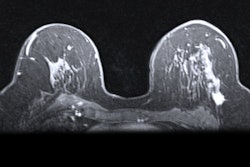

Sagittal T1-weighted fat-saturated contrast-enhanced MRI image of 71-year-old woman with history of breast cancer who presented for screening MRI. Arrow points to 4-mm focus in right breast at middle depth. MRI-guided core needle biopsy showed grade 1 invasive lobular carcinoma. All images courtesy of RSNA.